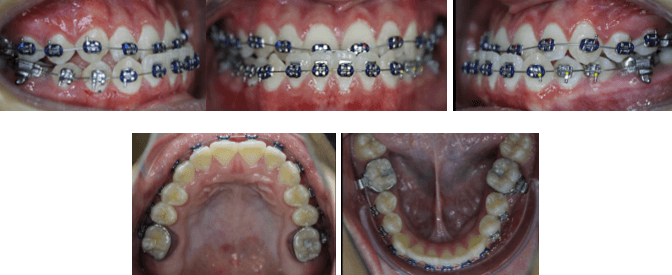

Fotografías Iniciales de Inicio de Tratamiento de Ortodoncia Prequirúrgica

Fotografías Intraorales Pre Quirúrgicas

El paciente se ha tratado bajo el concepto de Surgery First ya que se realizó la intervención quirúrgica de forma temprana con una mínima alineación y nivelación, evitando las desventajas de una larga etapa de ortodoncia prequirúrgica.